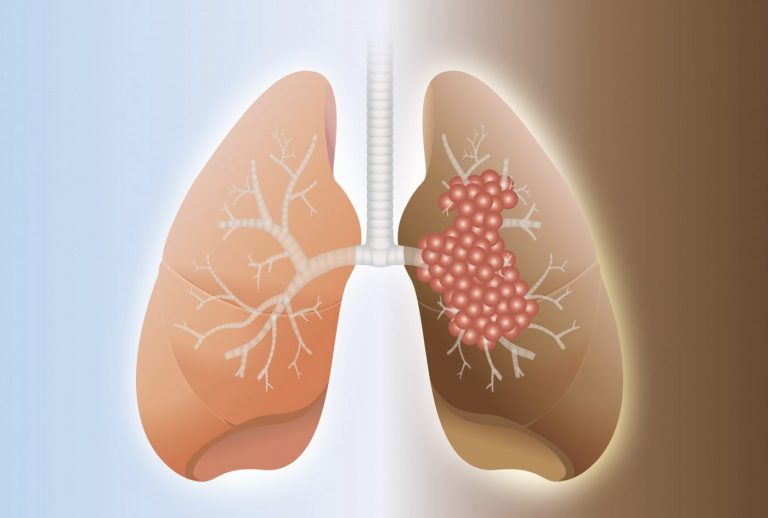

From www.shutterstock.com

Pulmonary Fibrosis Scarring Lungs Leading Difficulty Stock Vector (Royalty Free) 2289941867 Lung Scarring Treatment Pulmonary Fibrosis Treatment for pulmonary fibrosis is aimed at slowing the course of the disease, relieving symptoms and helping you stay active and healthy. Pulmonary fibrosis is scarring and thickening of the tissue around and between the air sacs called alveoli in the lungs. Treatments may slow down scarring and help. Doctors refer to lung scarring as “pulmonary fibrosis”. It can occur. Lung Scarring Treatment Pulmonary Fibrosis.

From stock.adobe.com

Pulmonary Fibrosis A lung disease that causes scarring. Stock Vector Adobe Stock Lung Scarring Treatment Pulmonary Fibrosis See the common types of pf. Treatments may slow down scarring and help. Scars on the lung tissue cause it to thicken and lose elasticity. There’s no way to cure lung scarring, but there are treatments for pulmonary fibrosis that can slow the progression of the. Treatment is aimed at preventing more lung scarring, managing symptoms, and helping you stay. Lung Scarring Treatment Pulmonary Fibrosis.